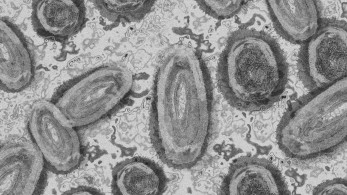

ΕΥΛΟΓΙΑ ΤΩΝ ΠΙΘΗΚΩΝ